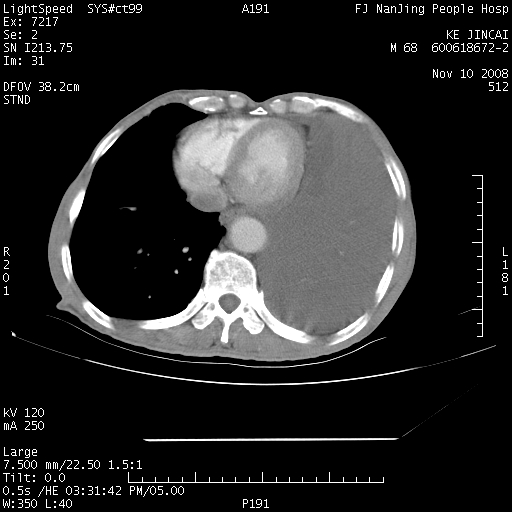

是个很有看头的病例,咋人气那么不旺?没多少人兴趣呢?这个病例几大怪:1   恶性肿瘤侵犯心肌左房怪,心肌一般不会被恶性肿瘤侵犯吧?2   左下肺均匀实变怪,内无含气,有别一般不张实变,含气肺泡完全为液体取代,而非一般不张实变的肺萎陷,冷不丁还以为是肿大的脾脏3   肿瘤本身怪,像tb肺不张4   这么有看头的病例没人气怪。呵呵。

左肺恶性肿瘤侵犯肺动脉,左心房内瘤栓,胸膜转移。

左肺恶性肿瘤侵犯肺动脉,左心房内瘤栓,胸膜转移,少见,学习了。